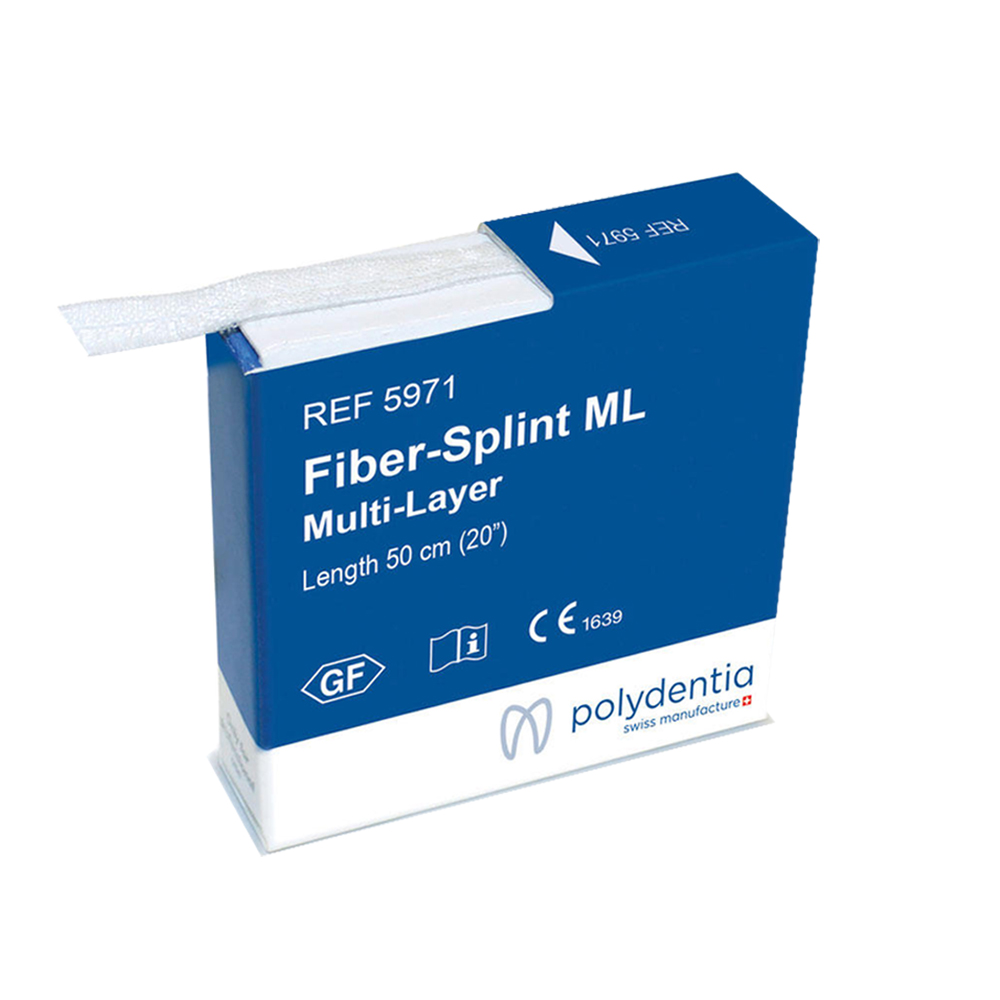

Versatile fiberglass ribbons for easy dental splinting, ensuring high aesthetic outcomes and efficient application

Polydentia Fiber-Splint is used for splinting and reinforcing dental restorations, providing strength and durability to weakened or fractured teeth.

Saturate the Fiber-Splint strip with the bonding agent (Fiber-Bond). Position the strip on the etched and bonded palatal/lingual surfaces. Fix it in p...